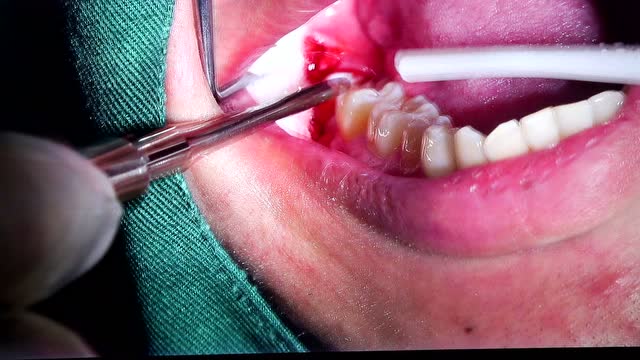

口腔科:超声骨刀微创拔牙|森海医院口腔科